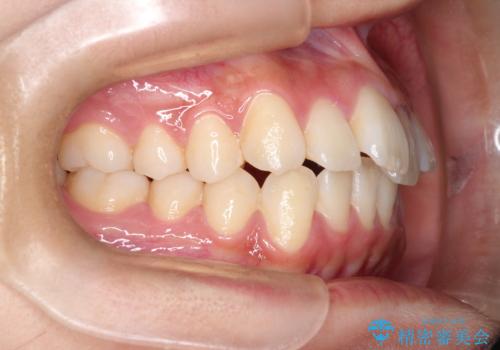

前歯の叢生・Ⅱ級咬合を改善|TADを用いた遠心移動+インビザライン矯正

- 前歯のガタガタと臼歯関係のⅡ級(上顎の歯列が前方にある状態)を改善するため、TAD(歯科矯正用アンカースクリュー)を使用したインビザライン矯正を計画しました。まずTADを上顎の適切な位置に設置し、それを固定源にして奥歯を後方(遠心)へ移動させ、十分なスペースを確保します。その後、インビザラインによるマウスピース矯正で前歯の歯列を整え、臼歯関係を正常化します。治療期間はおよそ1年半〜2年を想定しています。

前歯部の叢生(ガタガタ)と臼歯関係のズレを改善するため、抜歯をせずに奥歯を後方へ移動(遠心移動)させることを選択しました。TADという小型のアンカースクリューを顎骨に設置することで、確実かつ効率的に奥歯を後方へ移動させました。併せて透明で目立ちにくいインビザラインを用いることで、審美性を保ちながら治療を進めることが可能でした。患者様の負担が少ないマウスピース矯正と固定源のTADを組み合わせることで、抜歯することなく歯並びと噛み合わせを大幅に改善でき、大変ご満足いただけました。